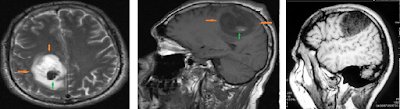

Ironicamente, apesar da maioria das premissas básicas da frenologia terem sido consideradas pseudociência, as leituras dos comportamentos e a sua relação com o crânio não foram. O princípio de que as funções específicas cerebrais estão localizadas em topografias determinadas é agora conhecimento comum demonstradas por técnicas modernas de imagem, como a ressonância magnética funcional (FMRI). Esta doutrina que possibilita a visualização precisa de uma determinada função quando ela está sendo realizada é chamada de localizacionismo cerebral.